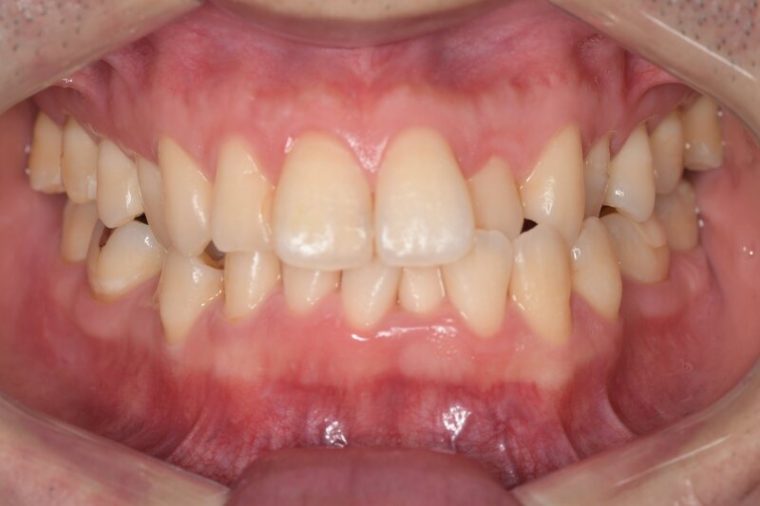

CASE 2

Before

After

基本情報

| 年齢・性別 | 30代・男性 |

| 主訴 | 歯石を取りたい |

| 治療内容 | 超音波スケーラーでの歯石除去 |

| 治療期間 | 60分 |

| 治療費 | 初診料を含め約4,500円 |

| リスク・副作用 | 歯ぐきに違和感や痛みを覚える場合がある。 1週間程度、歯を磨くといつもより出血することがある。 腫れていた歯ぐきが引き締まることで歯ぐきが下がった様に見える。 歯ぐきが下がることで歯がみしやすくなることがある。 一時的に歯の動揺(ゆれ)が増す場合がある。 |